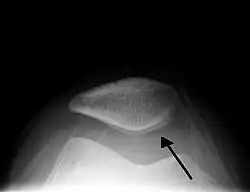

L’hydarthrose est l'accumulation anormale de liquide, spécialement de synovie, dans une articulation[1]. Cela survient essentiellement par augmentation de la sécrétion de synovie.

Elle est souvent localisée au genou (présence du signe du glaçon) et peut évoluer en kyste poplité.